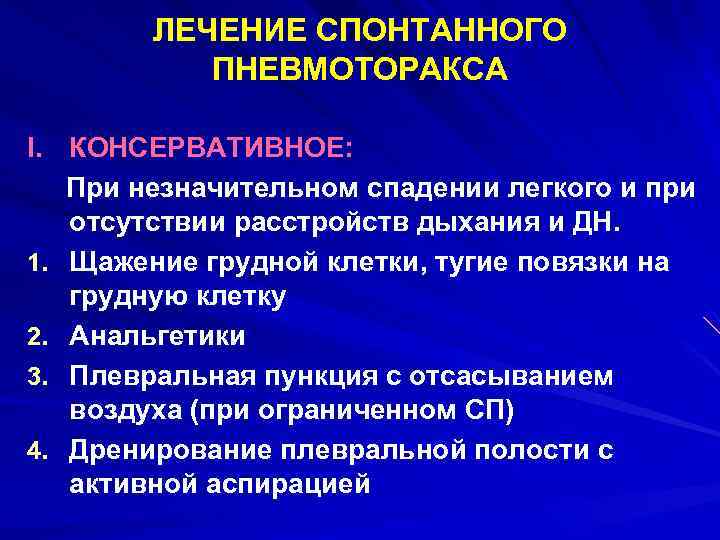

Раздел: Необычные решения